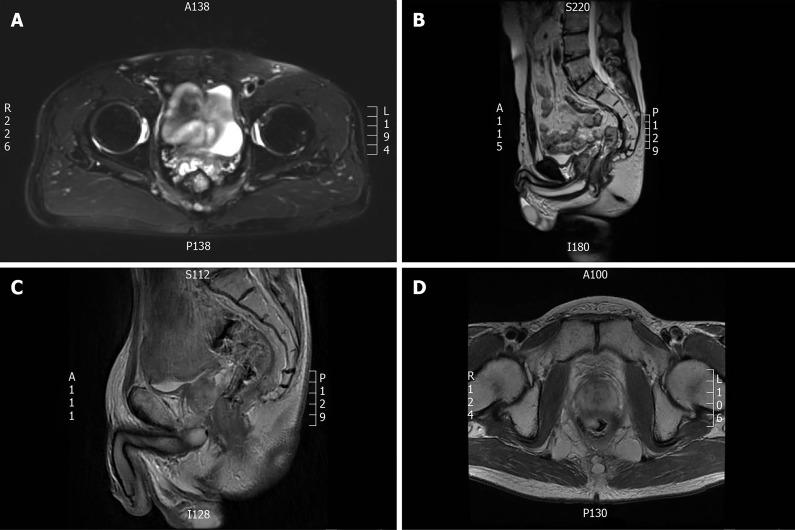

CASE SUMMARY

We analyzed the medical waiver and clinical data of 3 pilots with CRC, who had accepted the treatment at the Department of General Surgery, Air Force Medical Center (formerly, Air Force General Hospital) between 2013 and 2018. All 3 cases underwent a series of comprehensive treatment courses, including radical resection of CRC, sequential radiotherapy, and chemotherapy. The follow-up results were satisfactory. After passing through the high-risk period of recurrence and metastasis of CRC, they all were given a medical waiver for flying again. Medical observation showed that their flying operations were safe.